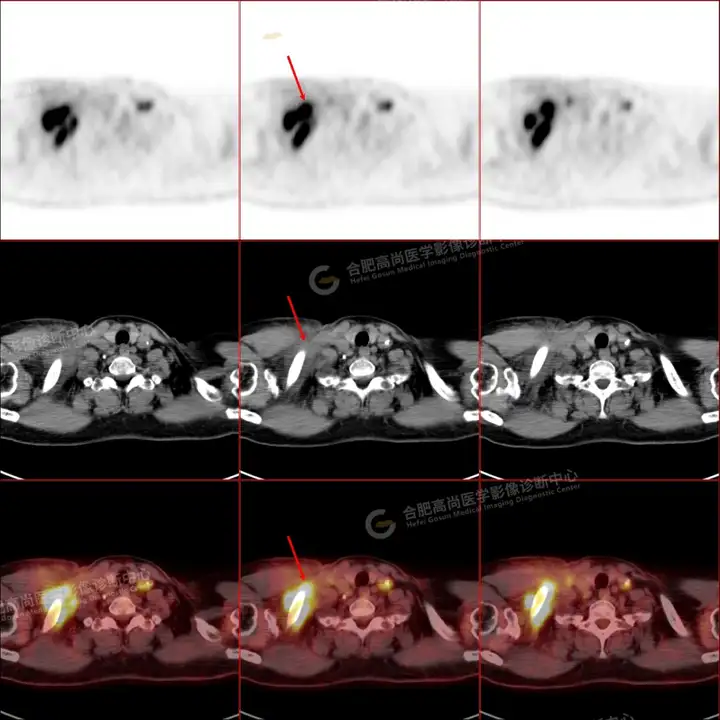

PETCT检查所示:图1、3-17全身多处(双上臂、胸背部、左侧乳腺、左侧腰部、腹壁、双侧臀部及双侧大腿)皮肤下结节及肿块样软组织密度灶,FDG代谢不同程度增高,双侧颈部、左侧锁骨区、纵隔内(1区)及双侧腋窝多发肿大淋巴结,FDG代谢明显增高,符合皮肤来源淋巴瘤。

图2右侧颈部包块切除术后,右侧锁骨区术区皮下片状密度增高灶,FDG代谢异常增高,考虑术后炎性反应。